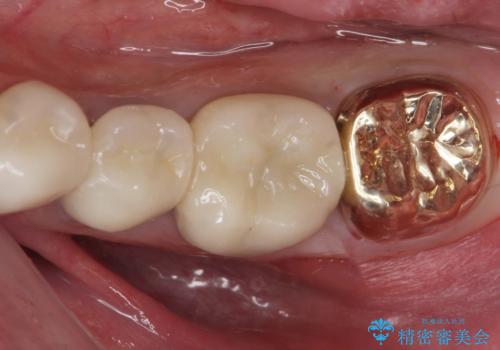

[ フルジルコニアクラウン治療 ] 銀歯を外したい

担当医 大元洋佑

![[ フルジルコニアクラウン治療 ] 銀歯を外したいの症例 治療前](https://seimitsushinbi.jp/wp/wp-content/uploads/2023/06/e91bc94295cd286b9a77624c761fc3dc-500x350.jpg?v=1685951434)

![[ フルジルコニアクラウン治療 ] 銀歯を外したいの症例 治療後](https://seimitsushinbi.jp/wp/wp-content/uploads/2023/06/5a59b739ff9adaba93515f667b19b84c-500x350.jpg?v=1685951438)